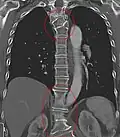

Mehrere angeborene Blockwirbel im Übergang von der Brust- zur Lendenwirbelsäule und Halbwirbel bei hemimetamerer Segmentverschiebung an der oberen Brustwirbelsäule. -